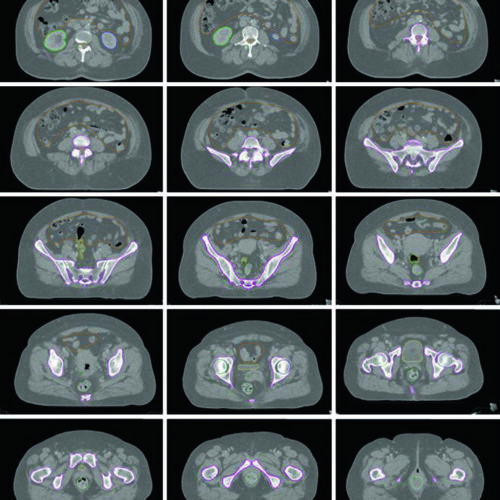

Delineamento de Volumes

Guias práticos de delineamento de volumes-alvo e órgãos de risco por sítio anatômico na radioterapia.